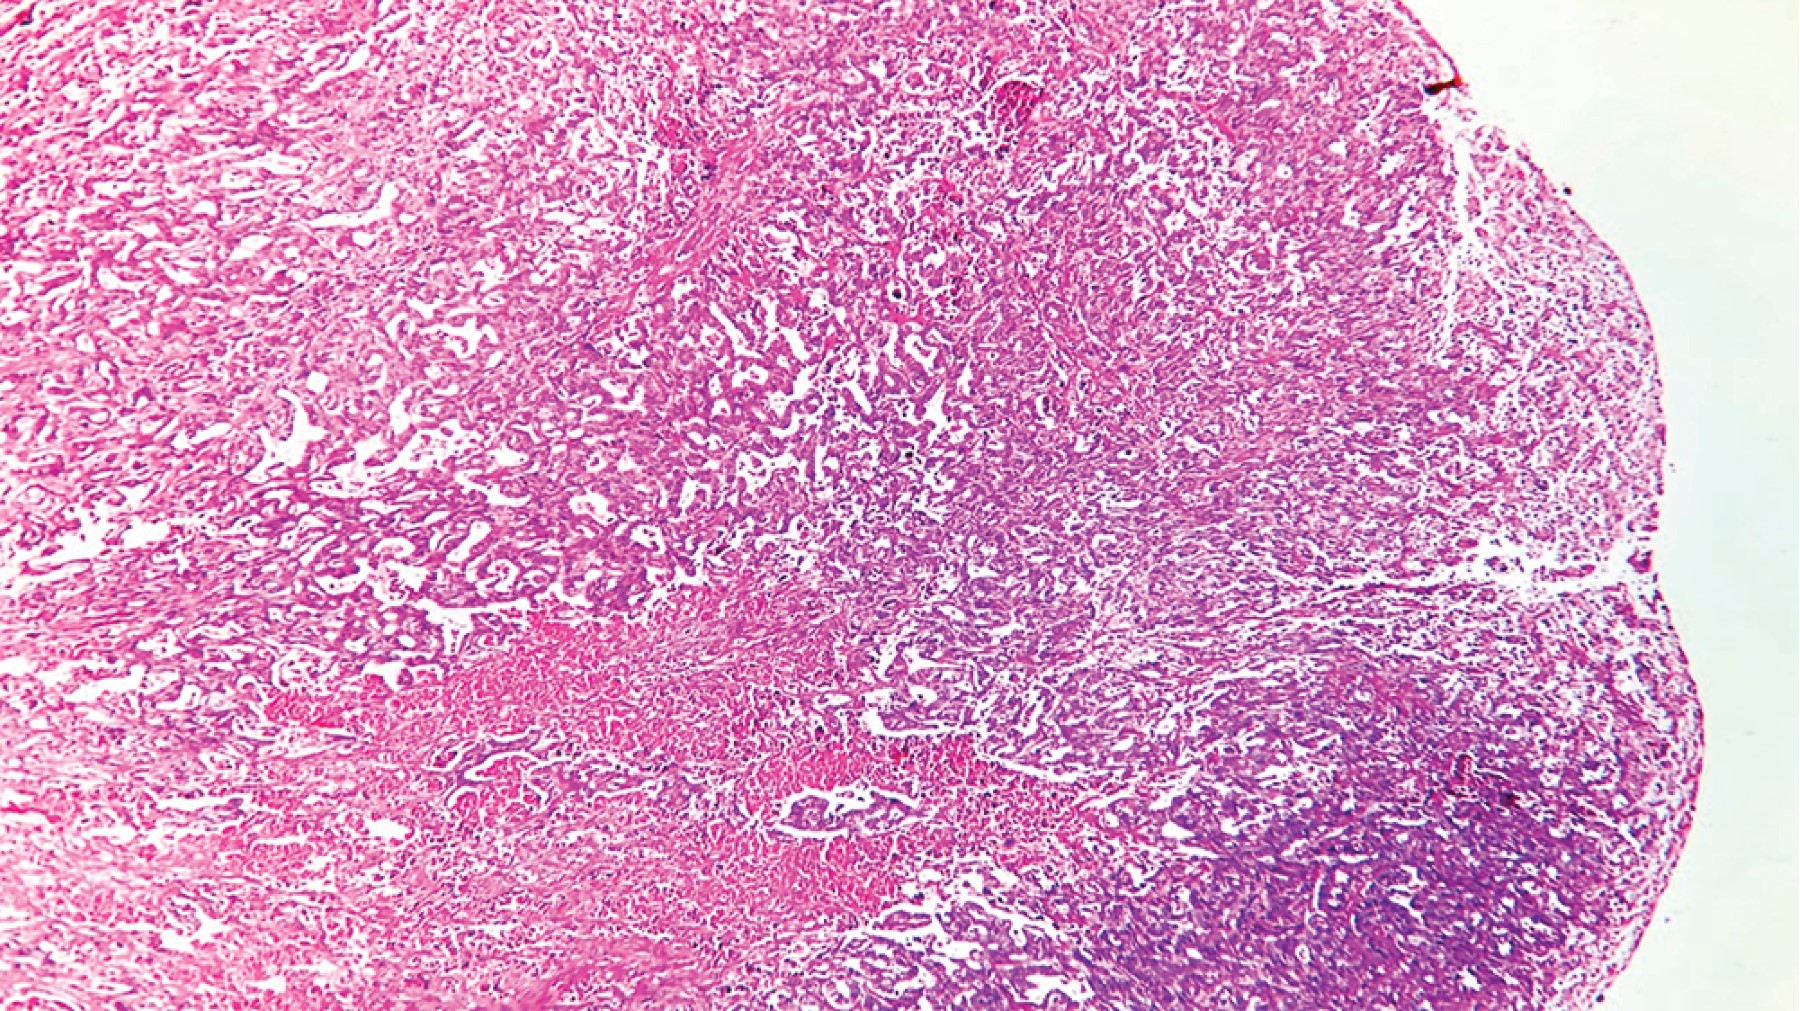

Introduction: rectal cancer can occur in young patients with no family history, so it is important to assess screening studies in the young population. Clinical case: 25-year-old male with no family history, goes to the emergency department due to a distal bowel obstruction with a history of 30 kg weight loss and diarrhea of six months' duration, imaging studies with an upper rectal lesion and secondary liver nodules. Discussion: results from studies worldwide support the benefits of changing the age of screening for colorectal cancer for patients of any age. The implementation of screening is intended to reduce mortality, but not incidence rates. Conclusions: it is necessary to take into account and assess the signs and symptoms of young patients who come to the consult with symptoms suggestive of a tumor and not wait for them to arrive at an emergency department with data of distal large intestine occlusion and think that cancer can be present also in young patients.

Figure 4